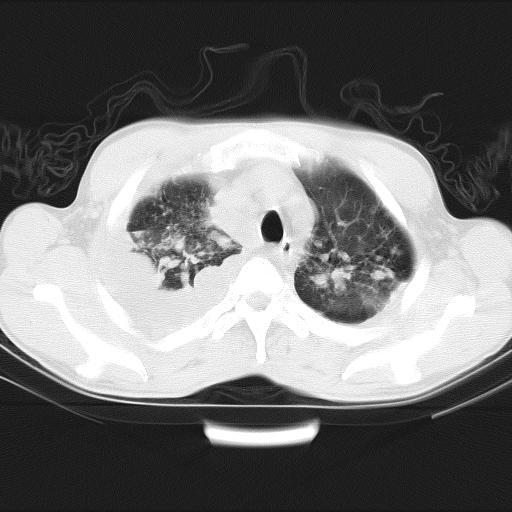

男性,44岁,结核病史多年。现胸闷气短,咳嗽,偶咳血。

右侧胸腔积液

右肺下叶不张

双肺多发结节影最分空洞形成考虑占位不除外结核

双肺陈旧性病变

1、右侧大量胸腔积液伴右肺压缩性膨胀不全,建议抽液治疗后复查 2、两肺继发性tb伴空洞形成。

1)两肺继发性肺结核伴空洞形成,左肺多发性结核球。2)右侧大量胸腔积液伴右肺部分膨胀不全。3)纵隔淋巴结肿大。